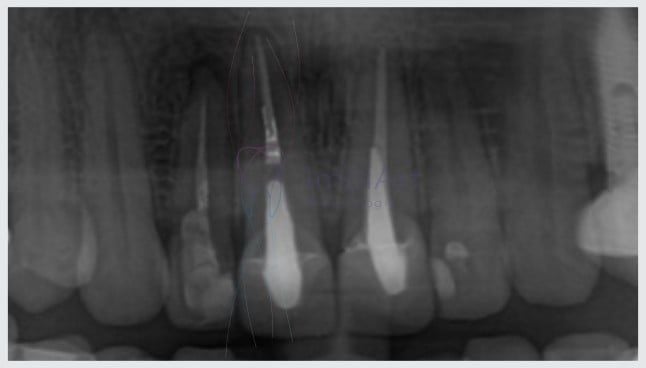

Tenho uma cárie, e agora? A cárie dentária é um tipo de lesão causada por bactérias presentes no biofilme, placa ou tártaro. A atividade bacteriana libera toxinas que, aos poucos, vão deteriorando o esmalte dentário e a lesão chega até a dentina, uma camada mais profunda e sensível dos dentes…